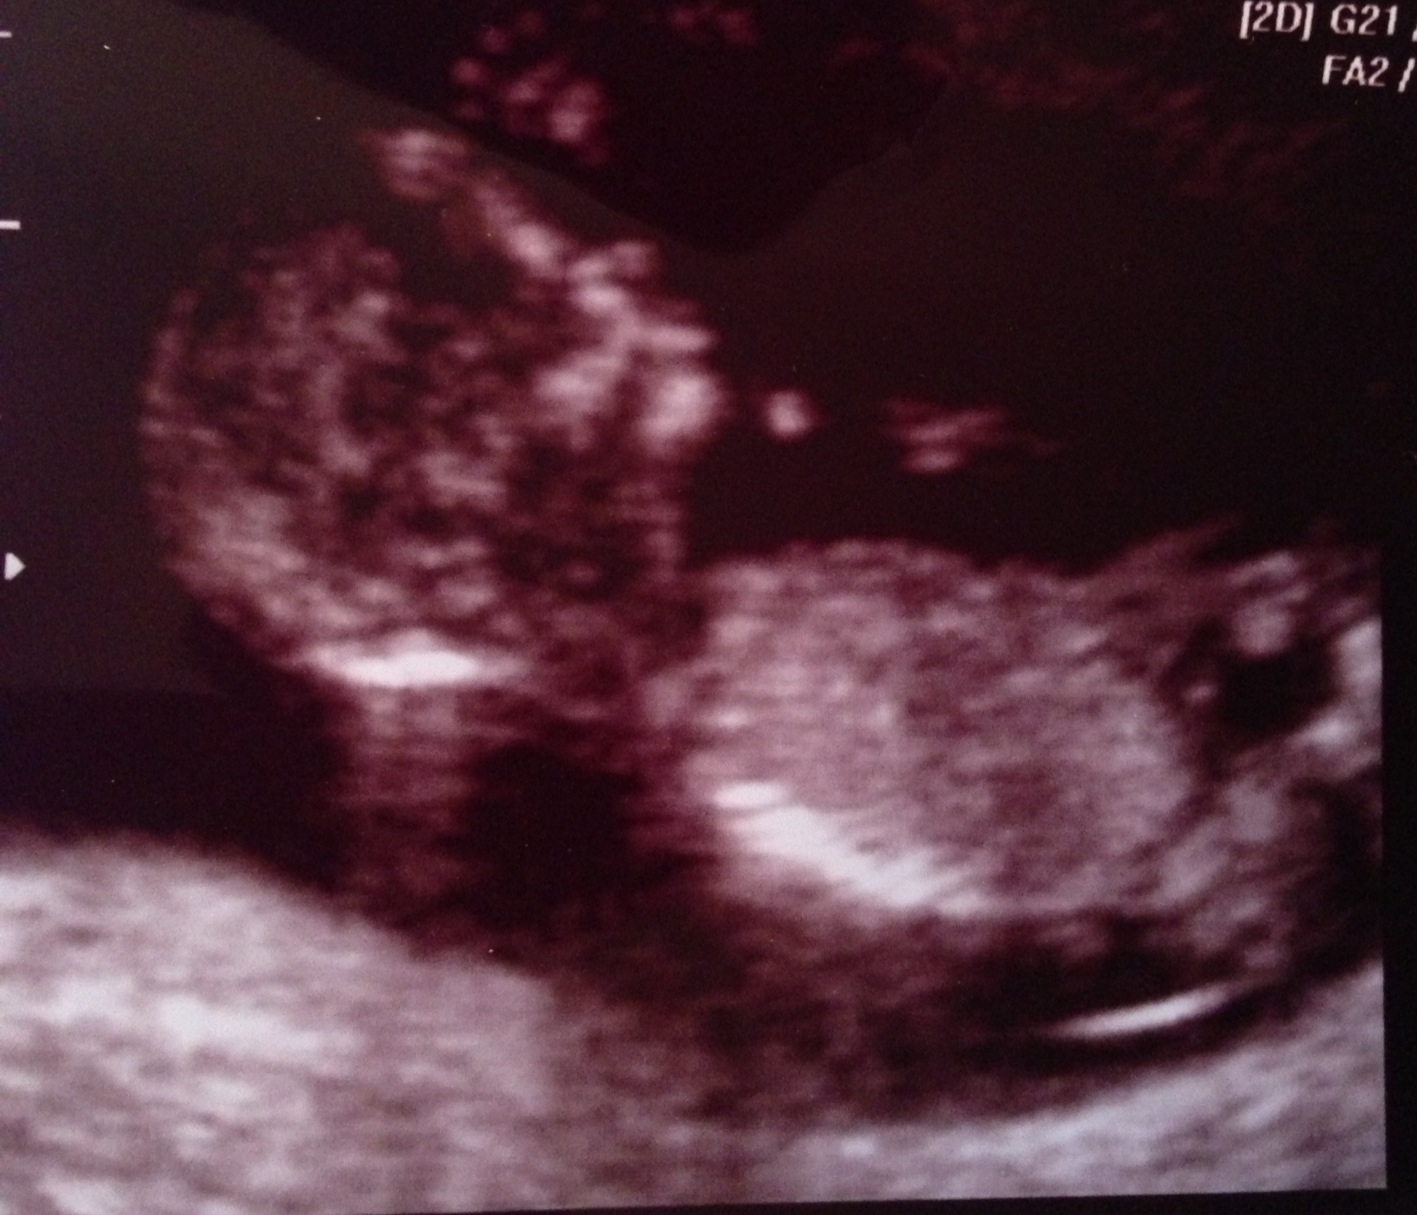

I just had a 12 week ultrasound and am very curious as to the sex of my baby. I will be happy either way. I would just like a healthy baby. Thank you for your help!

Last picture looks very boyish. Congrats!

If that last pic is in fact a nub, then BOY!

The last pic looks very boyish :DS: